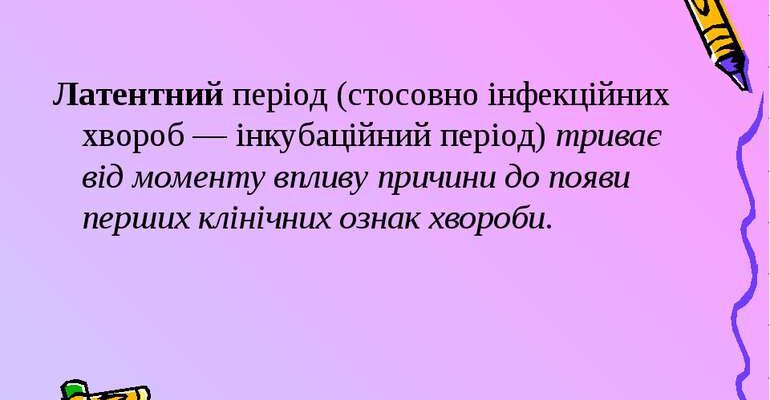

Латентний період: це що таке? Латентний період це частина життєвого циклу чи процесу, який може бути важко помітити або зрозуміти. Він схожий на прихований